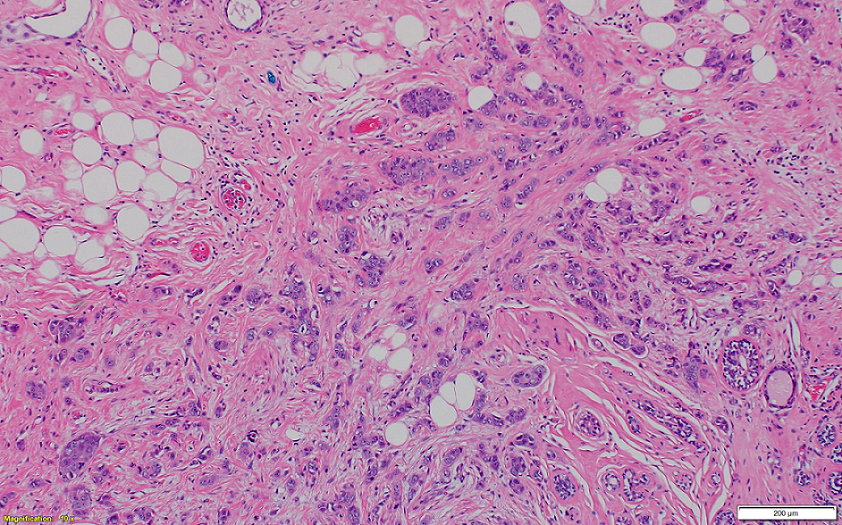

Cystic Lymphangioma of the Pancreas: About A Case and Literature Review

Dr Kouassi Armel Serge Kouame, Dr Aboulfeth El Mehdi, Dr Bouzroud Mohamed, Pr Najih Mohamed, Pr Kaoui Hakim, Pr Bounaim Ahmed

International Journal of Innovative Research in Medical Science·August 1, 2021